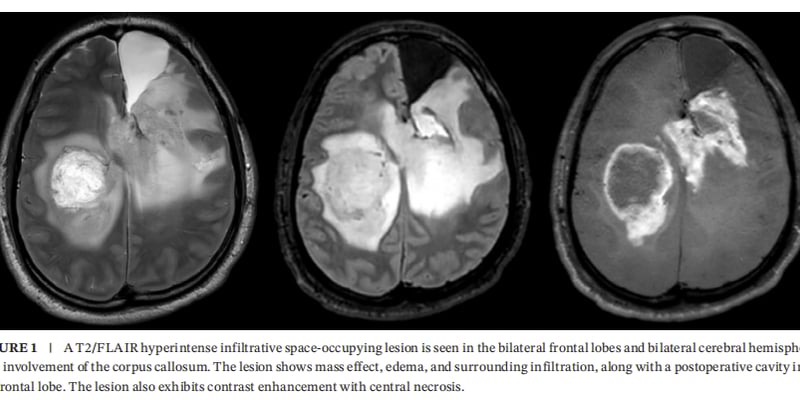

- MRI检查:MRI在软组织分辨率方面优于CT。**肝脏神经内分泌肿瘤**在MRI上通常表现为T1加权像低信号、T2加权像等或高信号、弥散加权成像(DWI)呈高信号。增强扫描时,病灶边缘或结节样强化,较大病灶中心可能出现无强化的坏死区。MRI的弥散加权成像(DWI)中的ADC值,可以间接反映肿瘤的恶性程度,分级越高的肿瘤通常ADC值越低,包膜完整性也越差。